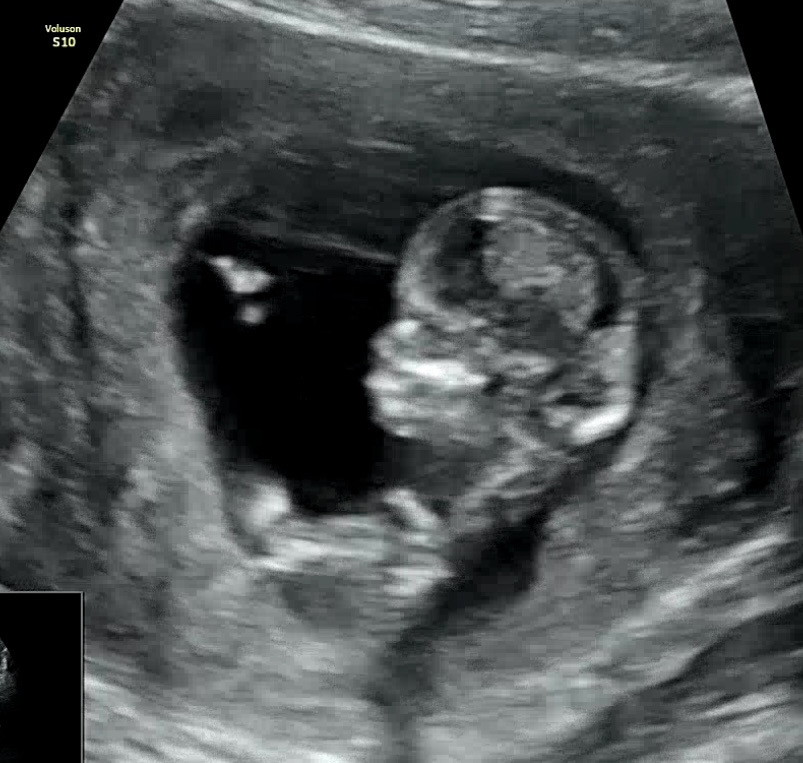

12주 코뼈

12주 3일차에 1차 기형아검사를 받으면서 목투명대 봤어요. 목투명대는 1.3mm로 정상 수치인데 코뼈가 잘 안보인다고 하시더라구요 .. 영상에서 잘 보이진 않긴한데 중간중간 코처럼 보이는게 있는거 같기도 해서 ㅠ 같이 봐주실 수 있을까요,,, 4주후에 오라고 했는데 불안해서 다음주에 다른 병원에서 초음파 봐보구 거기서도 동일하게 말하면 니프티 검사를 해야할 거 같아요 🥺

영상으로 전체적으로 보면 잘 안보이는데 저렇게 보일때가 잠깐잠깐 있더라구요...!!!! 맘이 조금 놓이네요 감사합니다 ㅎㅎ

저도 저기 코 모양 보이는것 같은데 왜 그럴까요..